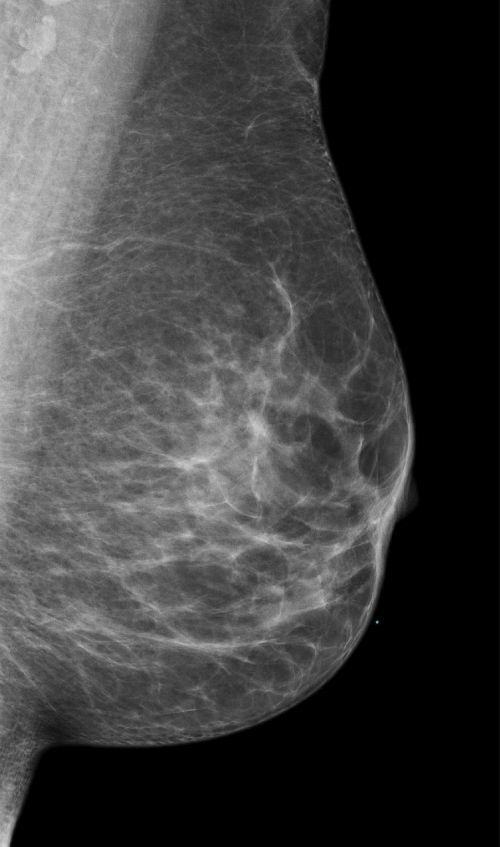

ACR-Klassifikation der Brustdichte in der Mammographie

Die ACR-Klassifikation der Brustdichte in der Mammographie ist ein System zur Einteilung der Brustgewebe in vier Kategorien, die von A bis D reichen. In Deutschland wird der anstatt ACR der Begriff Beurteilbarkeitsstufe verwendet.

Die Kategorie A steht für eine fast vollständig fettreiche Brust, die Kategorie B für eine überwiegend fettreiche Brust mit einigen fibroglandulären Bereichen, die Kategorie C für eine heterogen dichte Brust mit mehreren fibroglandulären Bereichen und die Kategorie D für eine extrem dichte Brust mit sehr wenig Fettgewebe.

Die Brustdichte ist ein wichtiger Faktor für die Erkennung von Brustkrebs, da dichtes Gewebe die Beurteilbarkeit der Mammographie erschweren und mögliche Tumoren verdecken kann. Die ACR-Klassifikation der Brustdichte in der Mammographie hilft den Radiologen, die Aussagekraft der Mammographie zu beurteilen. Je dichter das Drüsengewebe, desto sinnvoller ist eine zusätzliche Methode wie Mamma-Sonographie oder Mamma-MRT.